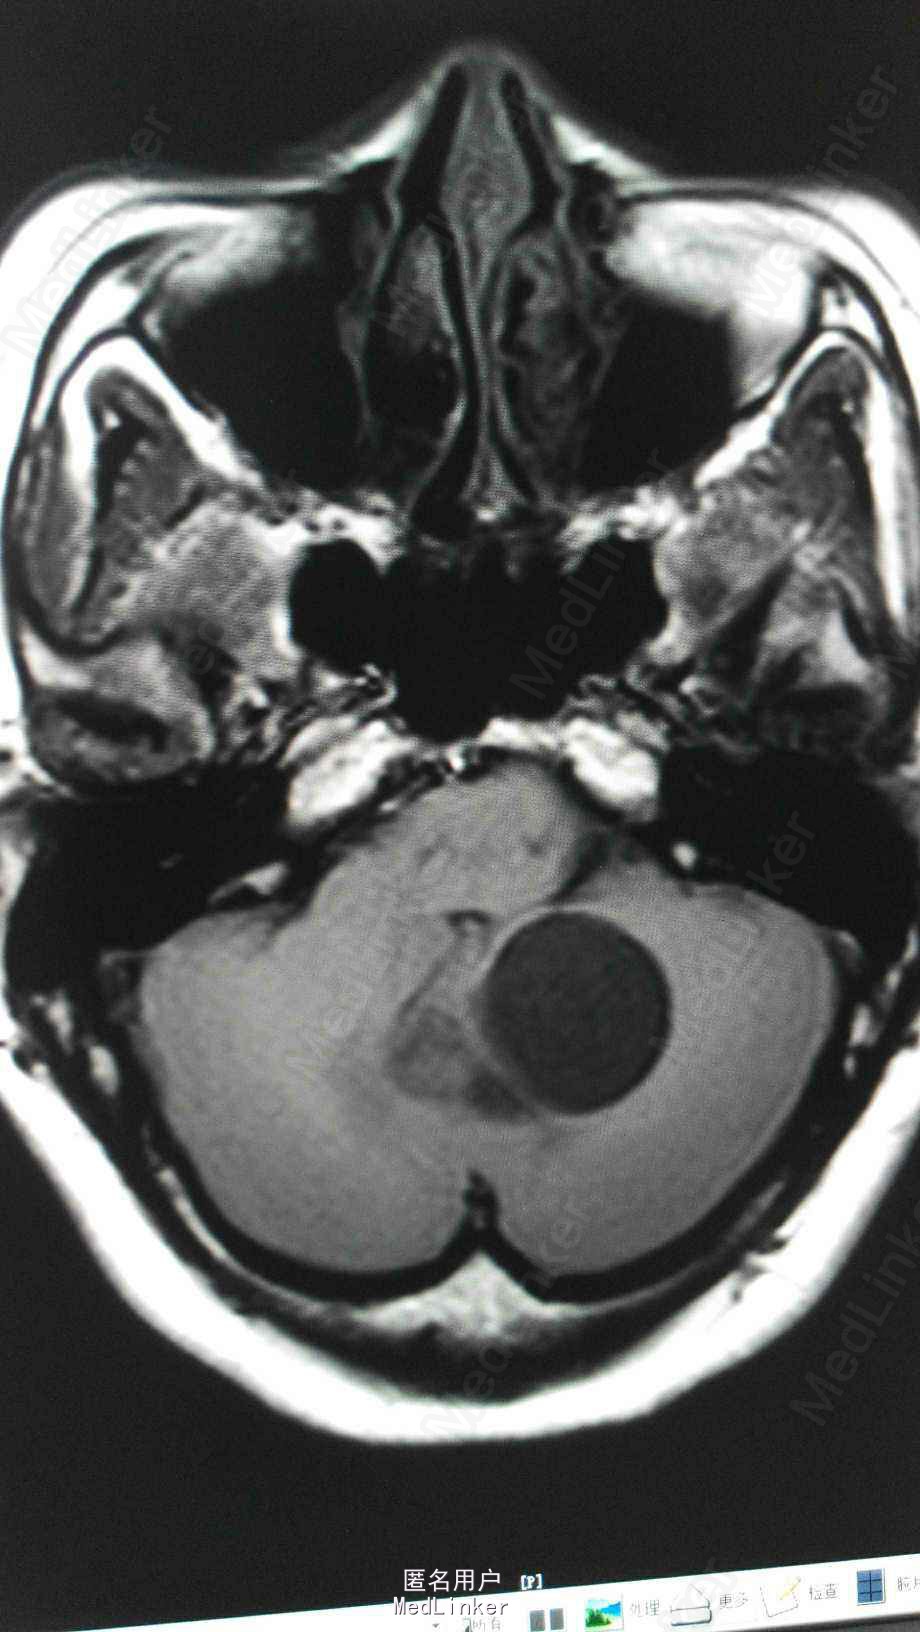

头颅MRA:小脑蚓部占位,血管母细胞溜可能性大;左椎动脉颅内段局部轻度狭窄;左侧大脑前动脉A1段稍细。